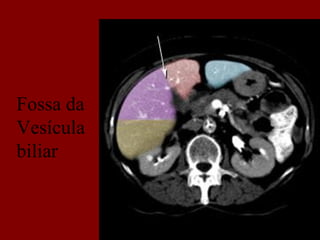

Fossa da

Vesícula

biliar

Ligamento

venoso

Ramo

Portal

segmento 3

principal

direito

Drenagen

Venosa

do segmento1